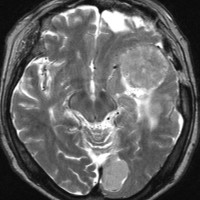

多発例,NF-2ではないもの

30代で下肢の局所てんかん発作で発見されました。テント上硬膜の腫瘍化です。数えれば総数で30個以上はあったでしょう。このタイプは手術で硬膜を広範囲切除(ほとんど全頭蓋冠)することで治すことができます。